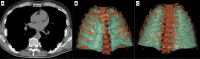

Fig. 16

Axial CT image shows bilateral pleural plaques in a 76-year-old male with previous asbestos exposure (A). Three-dimensional reconstructions show the typical distribution of the pleural plaques (B, C)